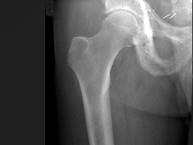

问题 男,56岁,右髋部疼痛,5年前被确诊为前列腺癌,结合图像,最可能的诊断是?(?)

选项 A.骨纤维异常增殖症 B.转移性骨肿瘤 C.畸形性骨炎 D.内生软骨瘤 E.非骨化性纤维瘤

答案 C